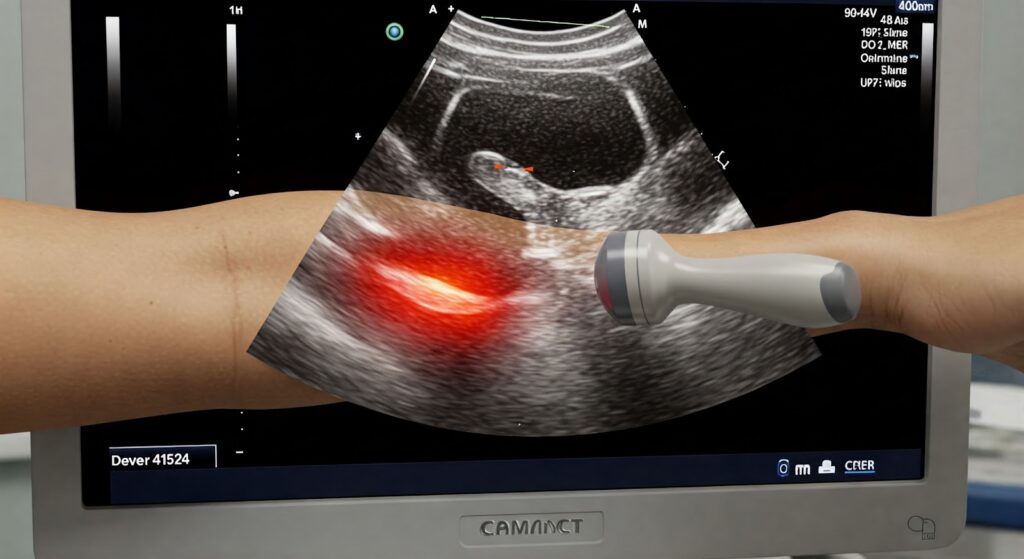

Soft tissue injuries, such as muscle tears, ligament sprains, and tendonitis, are common issues that many individuals face. Whether from sports, accidents, or overuse, these injuries can significantly affect daily life. To accurately assess and treat these conditions, healthcare providers use imaging tools, with ultrasound for soft tissue injuries standing out as a top choice. […]